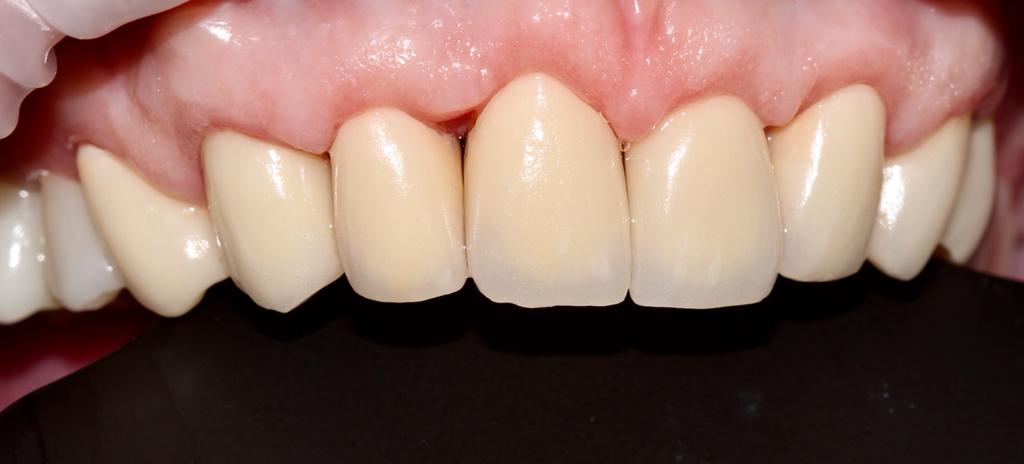

Снова виниры

Замена старых виниров темного цвета на более светлые по причине оголения шейки зуба.